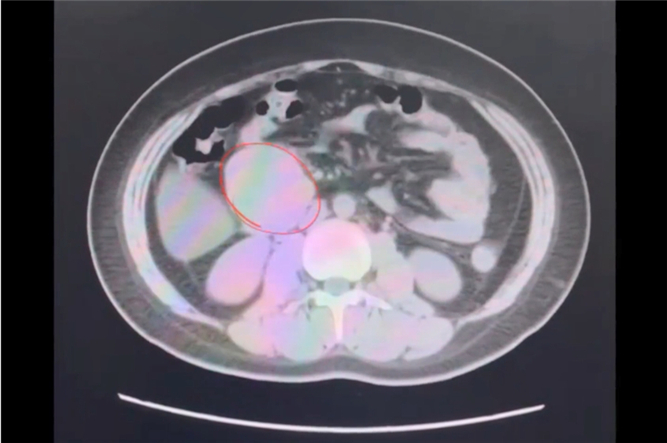

小愛(化名)經(jīng)歷剖宮產(chǎn)手術誕下了第一個孩子,成為了一名幸福的母親。然而,突如其來的疾病沖淡了新生命帶來的欣喜。產(chǎn)后2個月,小愛開始便血,出現(xiàn)重度貧血,血紅蛋白下降至30g/L,需要進行輸血支持治療。

經(jīng)過檢查發(fā)現(xiàn),原來小愛患上了十二指腸腫瘤,需要進行胰十二指腸切除術治療。由于胰頭部的解剖關系復雜,手術過程吻合多、難度高等多種原因,胰十二指腸根治切除術在肝膽外科領域屬于難度最高的標志性手術。